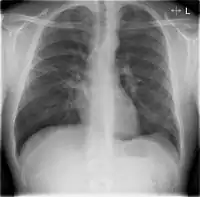

Chest X-rays of a CAP patient before (left) and after treatment

CAP is treated with an antibiotic that kills the infecting microorganism; treatment also aims at managing complications. If the causative microorganism is unidentified, which is often the case, the laboratory identifies the most effective antibiotic; this may take several days.

Chest X-rays and X-ray computed tomography (CT) can reveal areas of opacity (seen as white), indicating consolidation.[13] CAP does not always appear on x-rays, sometimes because the disease is in its initial stages or involves a part of the lung not clearly visible on x-ray. In some cases, chest CT can reveal pneumonia not seen on x-rays. However, congestive heart failure or other types of lung damage can mimic CAP on x-ray.[15]